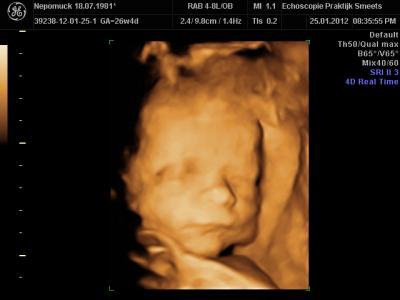

Huhu.. hatte gestern Termin zum 4D-Ultraschall.. Wie groß und schwer waren Eure Kleinen in der 27. SSW? Paul ist jetzt ca. 34 cm groß und 945 g schwer! GlG Iris Anbei ein Foto :-))

Bild zu Größe und Gewicht Baby - Forum für April - Mamis